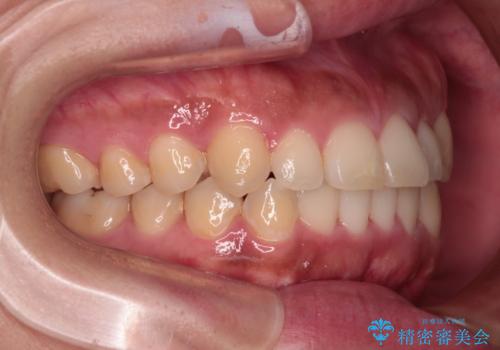

- 前歯の叢生と八重歯を気にして来院された患者様です。

目立たない装置を希望とのことで、インビザラインにて矯正治療を行うこととしました。

インビザライン単体で改善することも可能ですが、八重歯とその後方にある歯列を確実移動させないと、上下正中がずれてしまう可能性があります。

インビザライン単体での治療ではなく、カリエール・ディスタライザーという補助装置を併用して、より確実性を上げることとしました。

補助装置で八重歯を解消しながら、並行してインビザラインで歯列を整えることとしました。